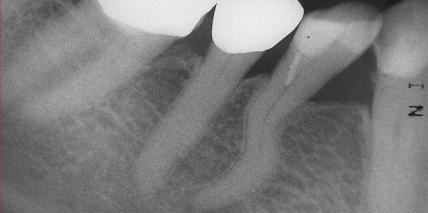

S-förmiger Kanalverlauf – eine besondere Herausforderung in der Endodontie

Jahr 2014, Ausgabe 04, Seite 12 Autoren: Dr. Friedrich Müller

S-shaped root – risks of a master challenge in endodontology

Jahr 2014, Ausgabe 03, Seite 18 Autoren: Dr Friedrich Müller, Germany